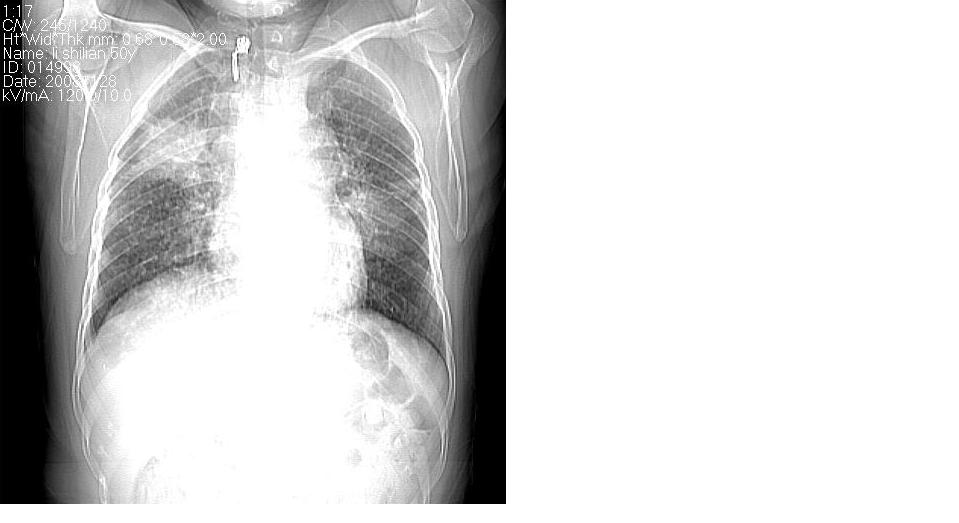

标题: CT16839:胸部CT平扫

女 50岁,在其他医院确诊肺癌.

支持 右肺上叶肺癌并两肺及纵隔转移。